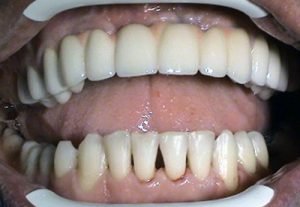

Prosthetic treatment in a toothless jawbone carried - 5 implants

1. PHASE - implant placement

2. PHASE - state before the provisional solution was made

3. PHASE - making a temporary solution

4.PHASE - implant placement